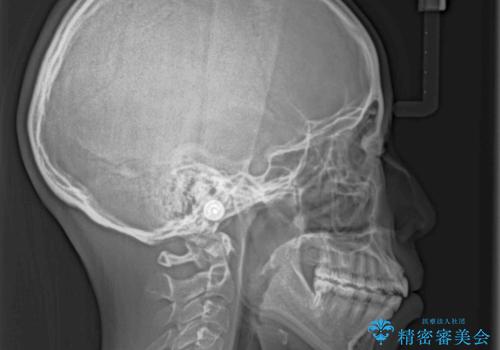

- 口元の突出感を気にして来院された患者様です。

上下左右の第一小臼歯4本を抜歯して口元を下げる治療計画としました。